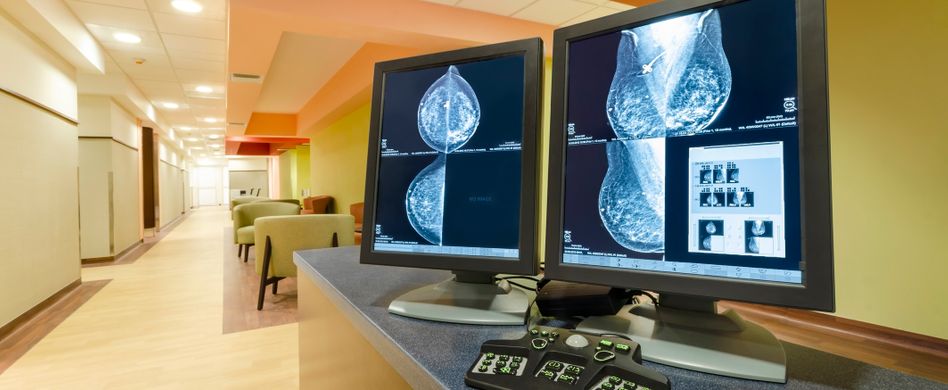

Brustkrebs erkennen: Mammografie

Frauen im Alter von 50 bis 69 Jahren haben im Zuge des bundesweiten Mammografie-Screening-Programms zudem alle zwei Jahre Anspruch auf eine Mammografie. Hierbei werden die Brüste einmal von oben nach unten und einmal schräg-seitlich geröngt, um Veränderungen im Brustgewebe zu erkennen. Dabei wird die Brust flach zwischen zwei Platten gepresst. Zwei speziell geschulte Fachärzte werten die Röntgenbilder unabhängig voneinander aus. Lässt sich ein Befund nicht eindeutig klären, schließen sich weitere Untersuchungen an, etwa die Ultraschalluntersuchung der Brust (Mammosonografie), eine Kernspintomografie der Brust (MRT) oder eine Gewebeentnahme aus der Brust (Biopsie).